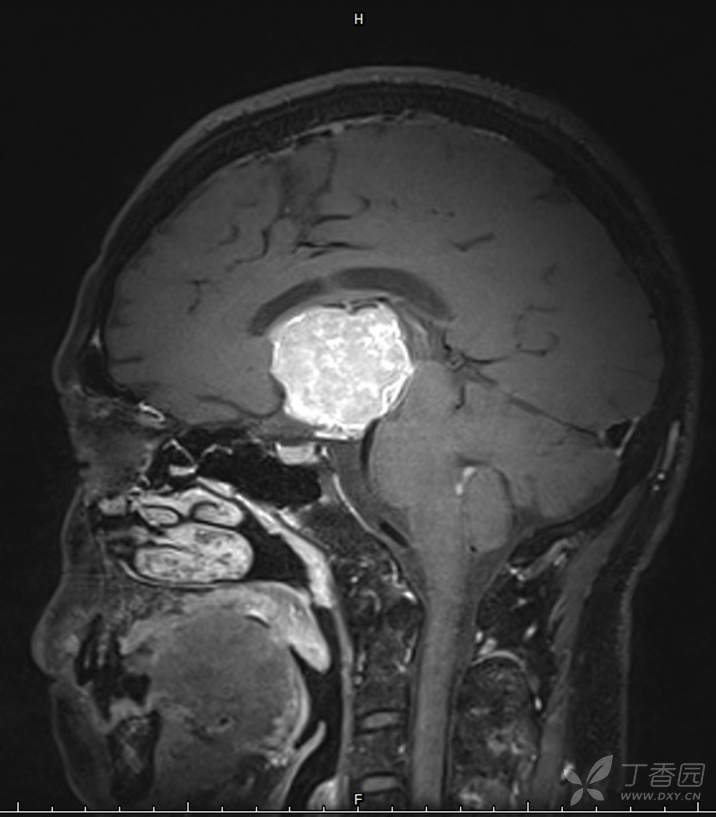

男,44岁,记忆力下降、乏力5月余,多尿3月余,CTMR全,疑难病例,能正确诊断吗?

图像不多,能诊断正确吗?有特征性吗?

增强